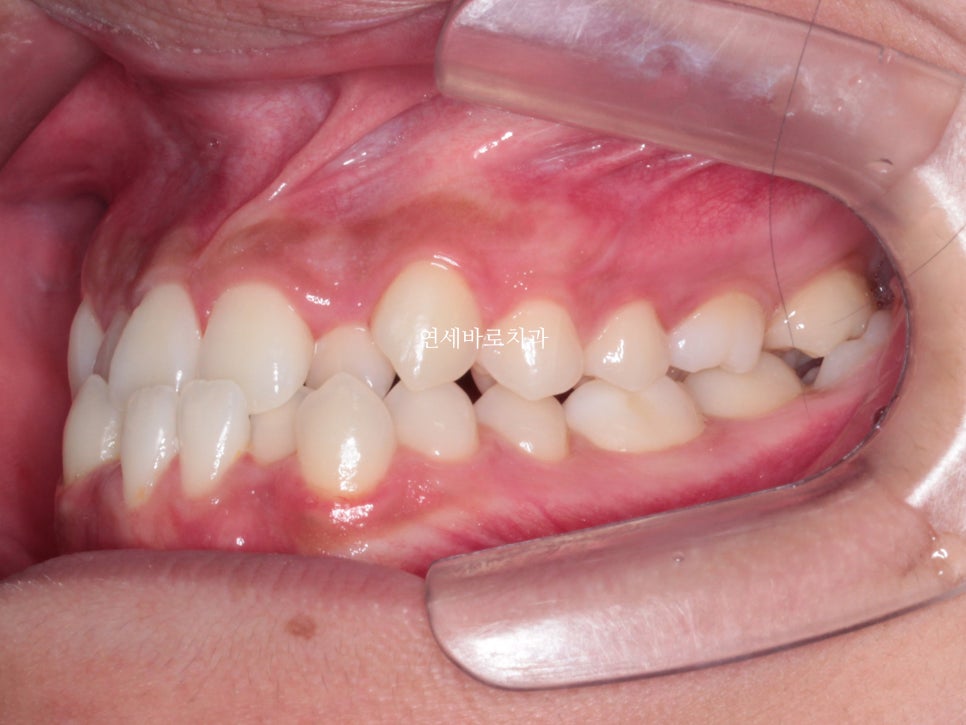

약 2년전쯤 왔던 친구입니다.

골격적인 3급 부정교합, 즉 '주걱턱'양상을 보이고 있었습니다.

또한 위아래 덧니가 심했어요.

특히 위쪽 어금니쪽은 치료가 쉽진 않았습니다.

위쪽 2개 치아의 발치 후 교정치료를 진행했습니다.

위쪽은 발치를 해야하기 때문에, 그리고 어금의 개선이 오래걸리기 때문에 아래쪽 장치를 거의 6개월이 지나서 붙이게 되었습니다.